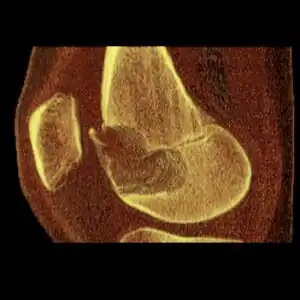

| Chondroblastoma[2] | ![]() | |